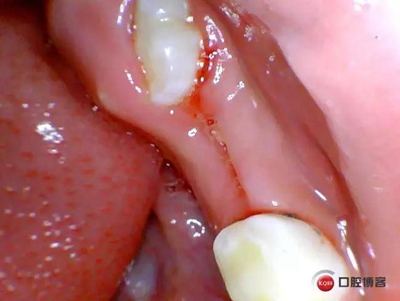

檢查:*75殘冠穿通髓腔,質(zhì)軟,叩診(++),溫度測試無反應(yīng),X線顯示遠(yuǎn)中根已完全吸收、近中根吸收至根頸1/3,且根尖可見低密度暗影。

處理:*75局麻下拔除,壓迫止血,不適隨診。

1.jpg